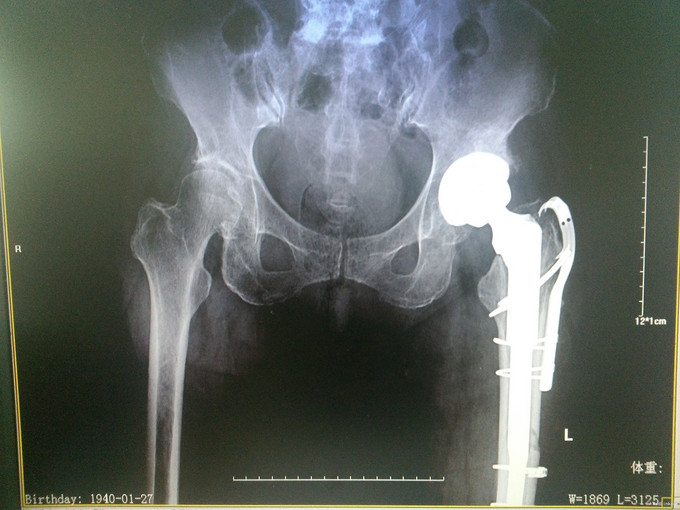

查体:左髋可见一长约8cm的手术疤痕,局部无明显肿胀,左下肢杠力消失,纵向叩击痛(+),肢端血运、感觉及活动良好。 辅助检查:骨盆X片:左股骨假体周围骨折。

诊断:假体周围骨折(左股骨假体柄周围骨折);高血压病;脑梗死后遗症;陈旧性肺结核 治疗:手术治疗[左侧股骨假体取出术+左侧股骨假体周围骨折切开复位钢板钢缆内固定术(zimmer)+左侧股骨假体置入术(MP,Link)] 术中探查及处理:股骨大粗隆崩裂,骨折线自近端向远端延伸至股骨中段,呈螺旋形,骨折块粉碎,移位明显。骨折断端可见淤血块。顺利取出假体柄后,复位骨折块,予复位钳临时固定后,予钢板钢缆(zimmer)加压捆扎。待骨折固定牢靠后,按照髋关节置换流程逐步扩髓,最后选择25omm长的14号假体(MP,Link)安装,36mm标准颈股骨头复位。测试各方向活动良好,松紧度合适。